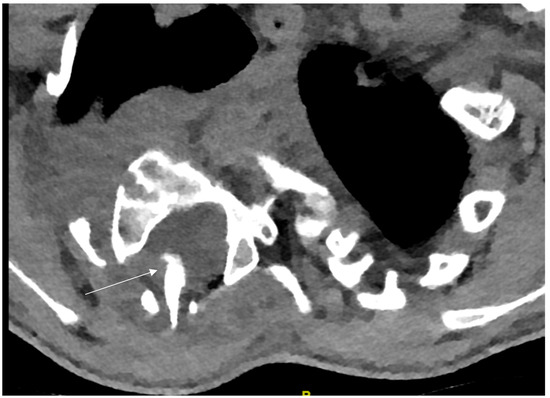

2.3.3. Imaging Modalities of Spinal Deformity in NF-1

3.2.2. Dystrophic Spinal Deformity

3.3. Surgical Treatment Methods